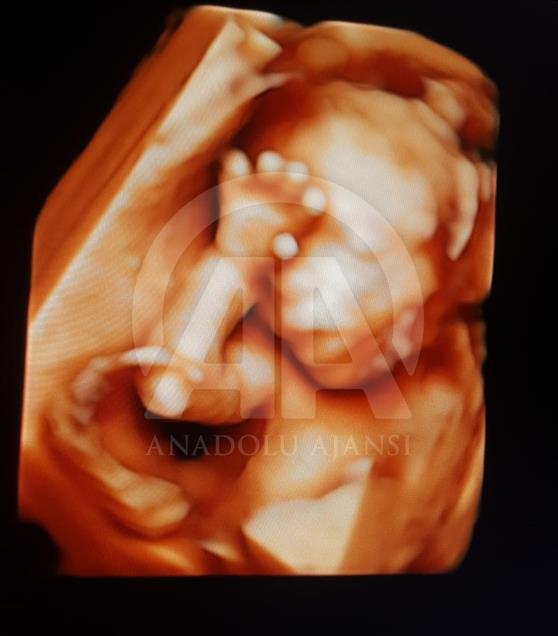

Anne karnındaki bebeklerin ilginç ultrason görüntülerini yakalayan ve bu görüntülerden özel bir köşe oluşturan kadın hastalıkları ve doğum uzmanı Doç. Dr. Gökalp Öner'in, yaklaşık 4 bin fotoğraflık koleksiyonu bulunuyor. Doç. Dr. Öner, AA muhabirine yaptığı açıklamada, sadece bir koleksiyon sahibi olmanın değil, anne ve babalara güzel bir hatıra oluşturmanın mutluluğunu da yaşadığını belirterek, "Doğumdan sonra aileler bizi ziyarete geldiği zaman kendi köşeleri olsun ve orada fotoğraf çektirelim istedik. Böylece, yaklaşık 4 bin ultrason fotoğrafına ulaştık." dedi. ( Müzahim Zahid Tüzün - Anadolu Ajansı )